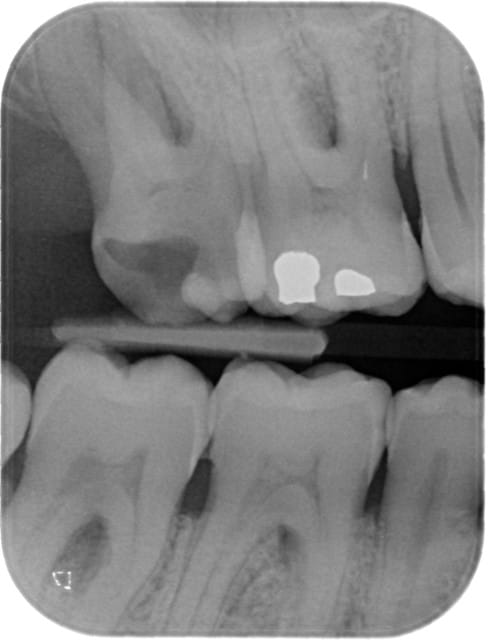

Première dent sur patient vivant !

Pas un cas très intéressant à montrer, seulement deux canaux, un vestibulaire et un palatin.

Plutôt une bonne impression, mais est-ce que ça m'a vraiment fait gagner du temps, je ne sais pas....

27waveonepost eocktj - Eugenol

27waveonepr  q0ln5s - Eugenol